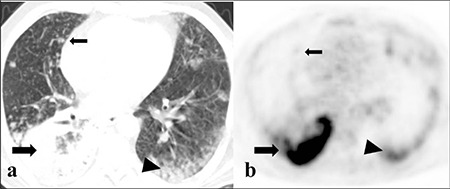

Methods: Tumors were divided into 2 groups according to CT appearance: Group 1: nodular-type tumor; group 2: mass- or pneumonic-type tumor. Unilateral and bilateral multifocal diseases were detected. Clinicopathological characteristics and PET/CT findings were compared between IMAs and LPAs, as well as between survivors and non-survivors.

Results: We included 43 patients with IMA and 14 with LPA. Tumor size (p=0.003), incidence of mass/pneumonic type (p=0.011), and bilateral lung involvement (p=0.049) were higher in IMAs than in LPAs. IMAs had more advanced T, M, and Tumor, Node, and Metastasis stages than in LPAs (p=0.048, p=0.049, and p=0.022, respectively). There was no statistically significant difference in maximum standardized uptake value (SUVmax) between the IMA and LPA (p=0.078). The SUV was significantly lower in the nodular group than in the mass/pneumonic-type group (p=0.0001). A total of 11 patients died, of whom SUVmax values were significantly higher in these patients (p=0.031). Male gender (p=0.0001), rate of stage III-IV (p=0.0001), T3-T4 (p=0.021), M1 stages (p=0.0001), multifocality (p=0.0001), and bilateral lung involvement (p=0.0001) were higher in non-survivor.

Conclusions: Although CT images were useful for the differential diagnosis of LPAs and IMAs, SUVmax was not helpful for differentiation of these 2 groups. However, both 18F-FDG uptake and CT findings may play an important role in predicting prognosis in these patients.